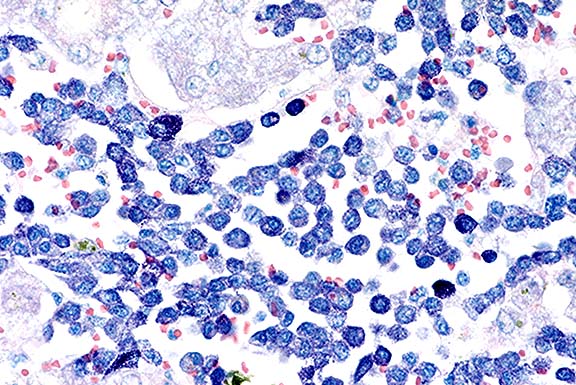

Case 9-2b. The mast cells contain sparse to numerous reddish-purple (metachromatic) granules in the cytoplasm. Giemsa. 40X

AFIP Diagnoses: 1. Liver: Mast cell tumor, malignant, Domestic Shorthair cat, feline. 2. Liver: Necrosis, coagulative, centrilobular, diffuse.

This case is an example of systemic mastocytosis in a cat. Metachromatic cytoplasmic granules were easily demonstrated in neoplastic mast cells with toluidine blue or Giemsa stains. Although gastroduodenal ulcers (probably secondary to histamine release) can develop in cats with this disease, none were found in this case. Disseminated intravascular coagulopathy may have contributed to the terminal clinical and hematologic findings.